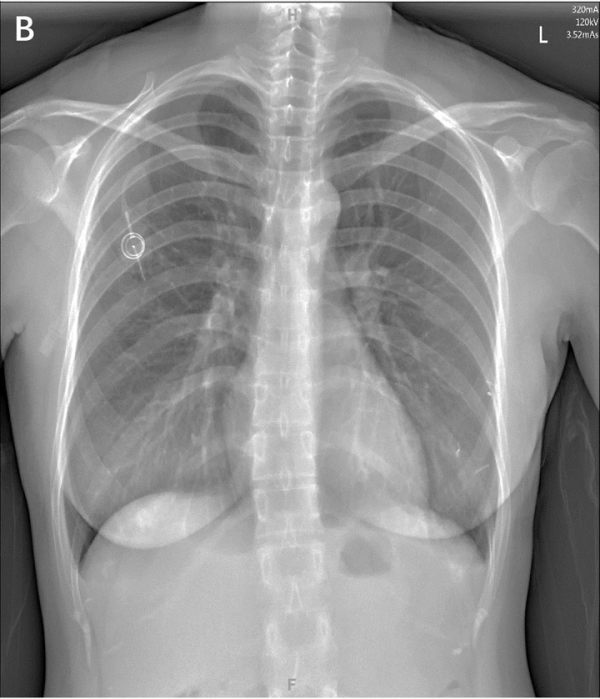

胸壁港最常见的是经『颈内静脉』或『锁骨下静脉』置入[2-3]

▲ 胸壁输液港的方式及对比